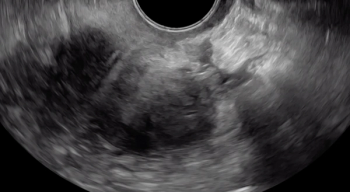

The beginning of the clip depicts a thin hyperechoic layer just deep to the vagina, which represents the rectouterine pouch peritoneum.

Following the hypoechoic layer of the bowel wall throughout the clip, viewers can appreciate the consistency of the thickness and echogenicity of this layer.